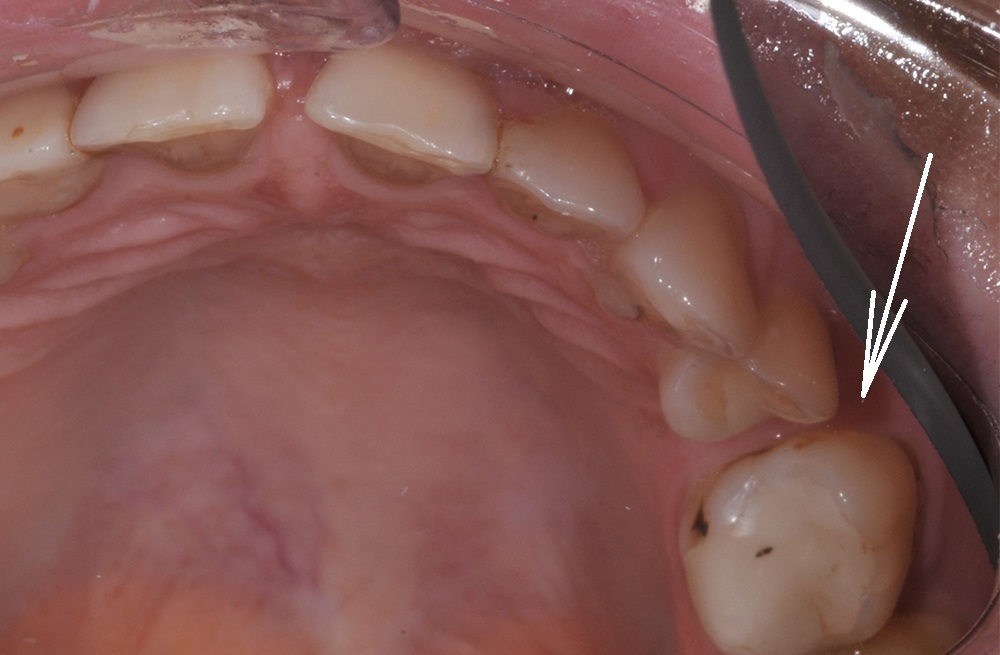

Подготовка места для импланта через устранение смещения зубов с помощью брекетов на минивинтах